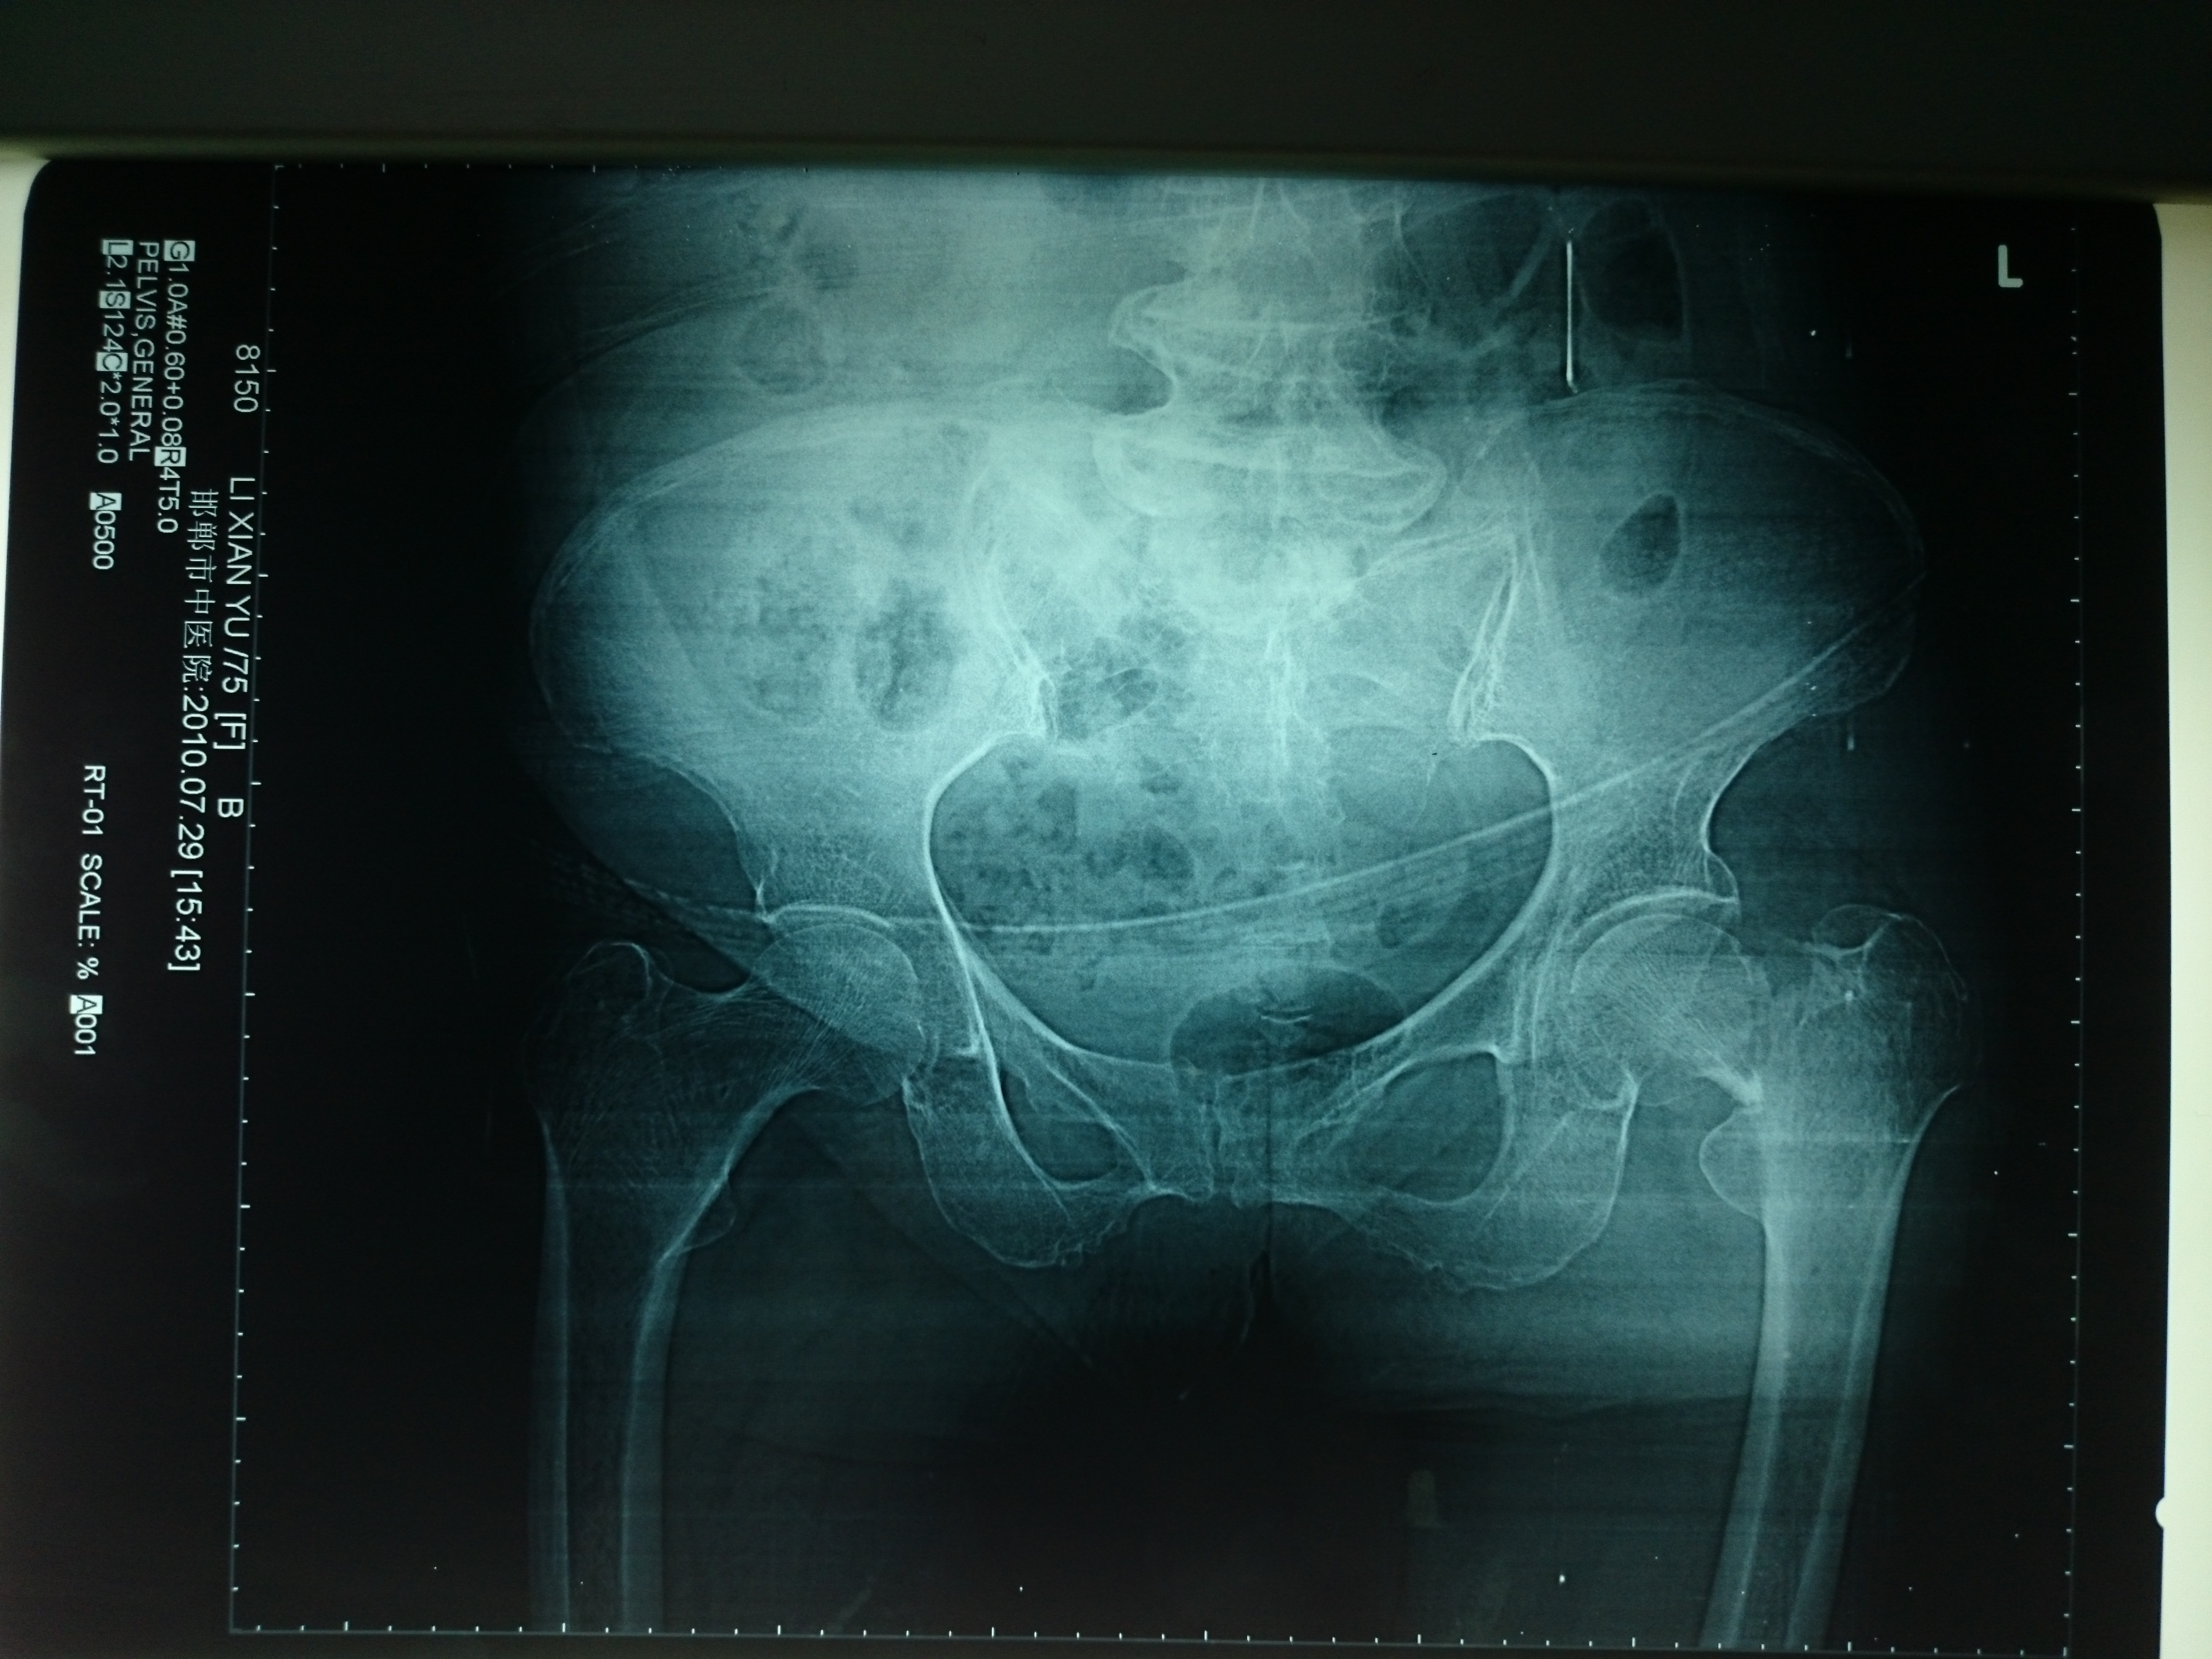

首页 > 张恒云工作室 > 影像资料 二十一